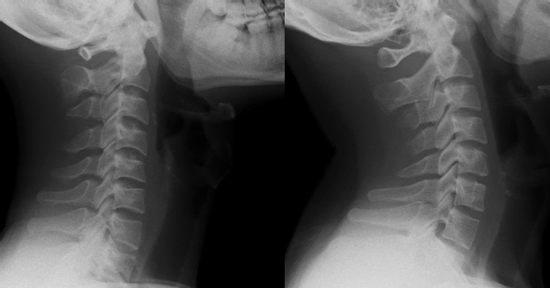

Nam thanh niên cột sống 'thẳng như cây gậy' vì thói quen triệu người mắc

Một nam nhân viên văn phòng 26 tuổi đã phải tìm đến bác sĩ vì tình trạng đau cổ vai gáy kéo dài. Kết quả chiếu chụp ghi nhận cột sống của bệnh nhân "thẳng như cây gậy".